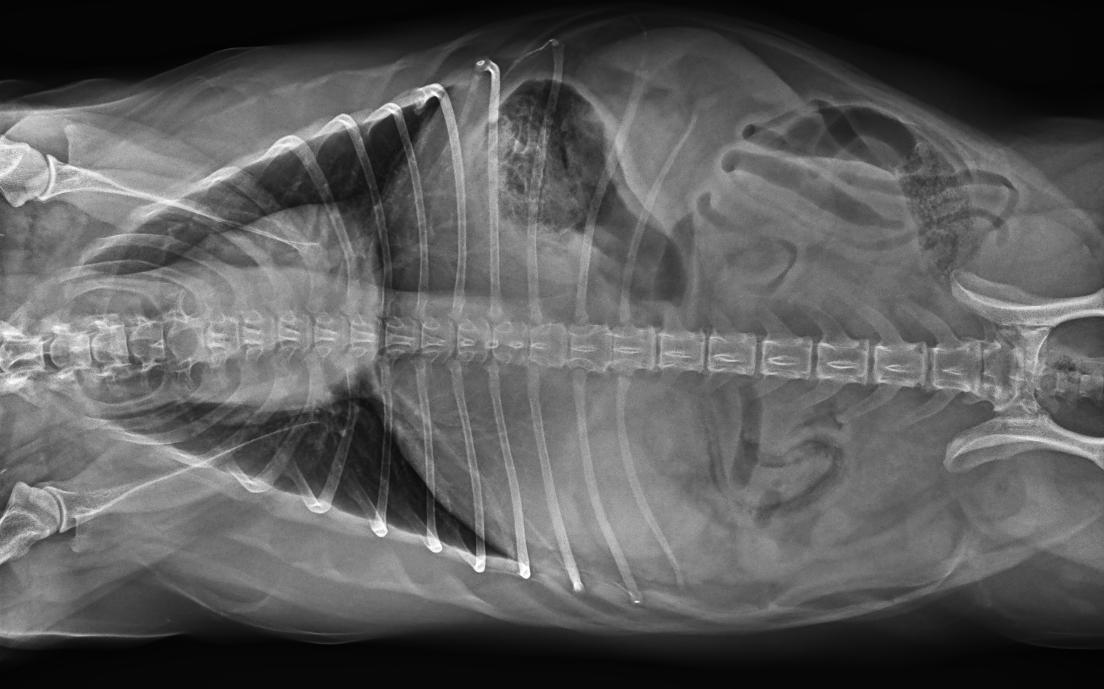

● 17*17大尺寸平板探測器,獲得高質(zhì)量圖像

● 優(yōu)異的空間分辨率及信噪比,提升圖像質(zhì)量

● 采用線(xiàn)噪聲消除技術(shù),使成像質(zhì)量提升40%

● 智能高效的圖像處理軟件,大幅提升圖像質(zhì)量